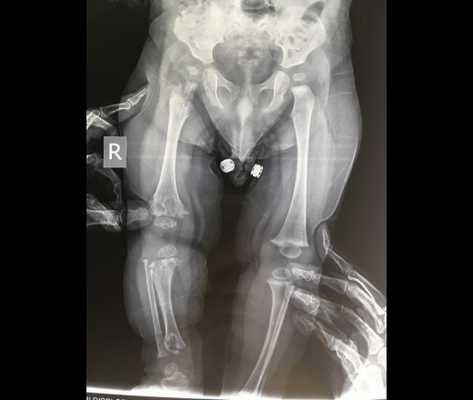

Рентгенологически у больных диастрофической дисплазией определяется уменьшение относительной длины трубчатых костей конечностей, часто сочетающееся с их дугообразной деформацией. Выявляются расширение метафизов, деформация головок бедренных костей, подвывихи и вывихи крупных суставов (коленных, локтевых, тазобедренных). Пястные кости и фаланги пальцев нередко укорочены, аналогичные изменения просматриваются и на костях плюсны. Практически всегда при диастрофической дисплазии обнаруживаются искривления позвоночника - сколиоз и кифоз различной степени выраженности. Молекулярно-генетическая диагностика заболевания сводится к прямому секвенированию гена SLC26A2 с целью подтверждения характерных генетических дефектов. Этот метод позволяет наиболее точно дифференцировать диастрофическую дисплазию от других скелетных аномалий, обусловленных мутациями SLC26A2.